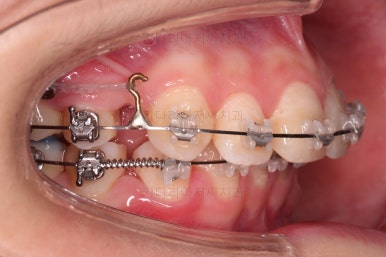

연산동치아교정 선택한 장치는 엠파워 클리어라고 하는 자가결찰 세라믹 장치입니다.

치아 갯수를 맞추고 튀어나온 앞니를 넣기 위해서 윗니 중간의 작은 어금니를 발치를 했고요.

아래는 통째로 앞으로 끌고 나오기로 했습니다.

아래턱은 아쉽게도 성장 시킬 수 있는 나이는 지났고, 대신 가능한 선에서 아랫니를 앞으로 빼보기로 했습니다.

윗니는 틈을 점점 줄여가고요.

아랫니는 중간에 오히려 틈이 생기고 있죠?

이런 효과로 위아래 앞니는 급속도로 가까워지게 됩니다.

아랫니는 이후에 어금니를 앞으로 당겨오면서 빈공간을 줄여 나갑니다.